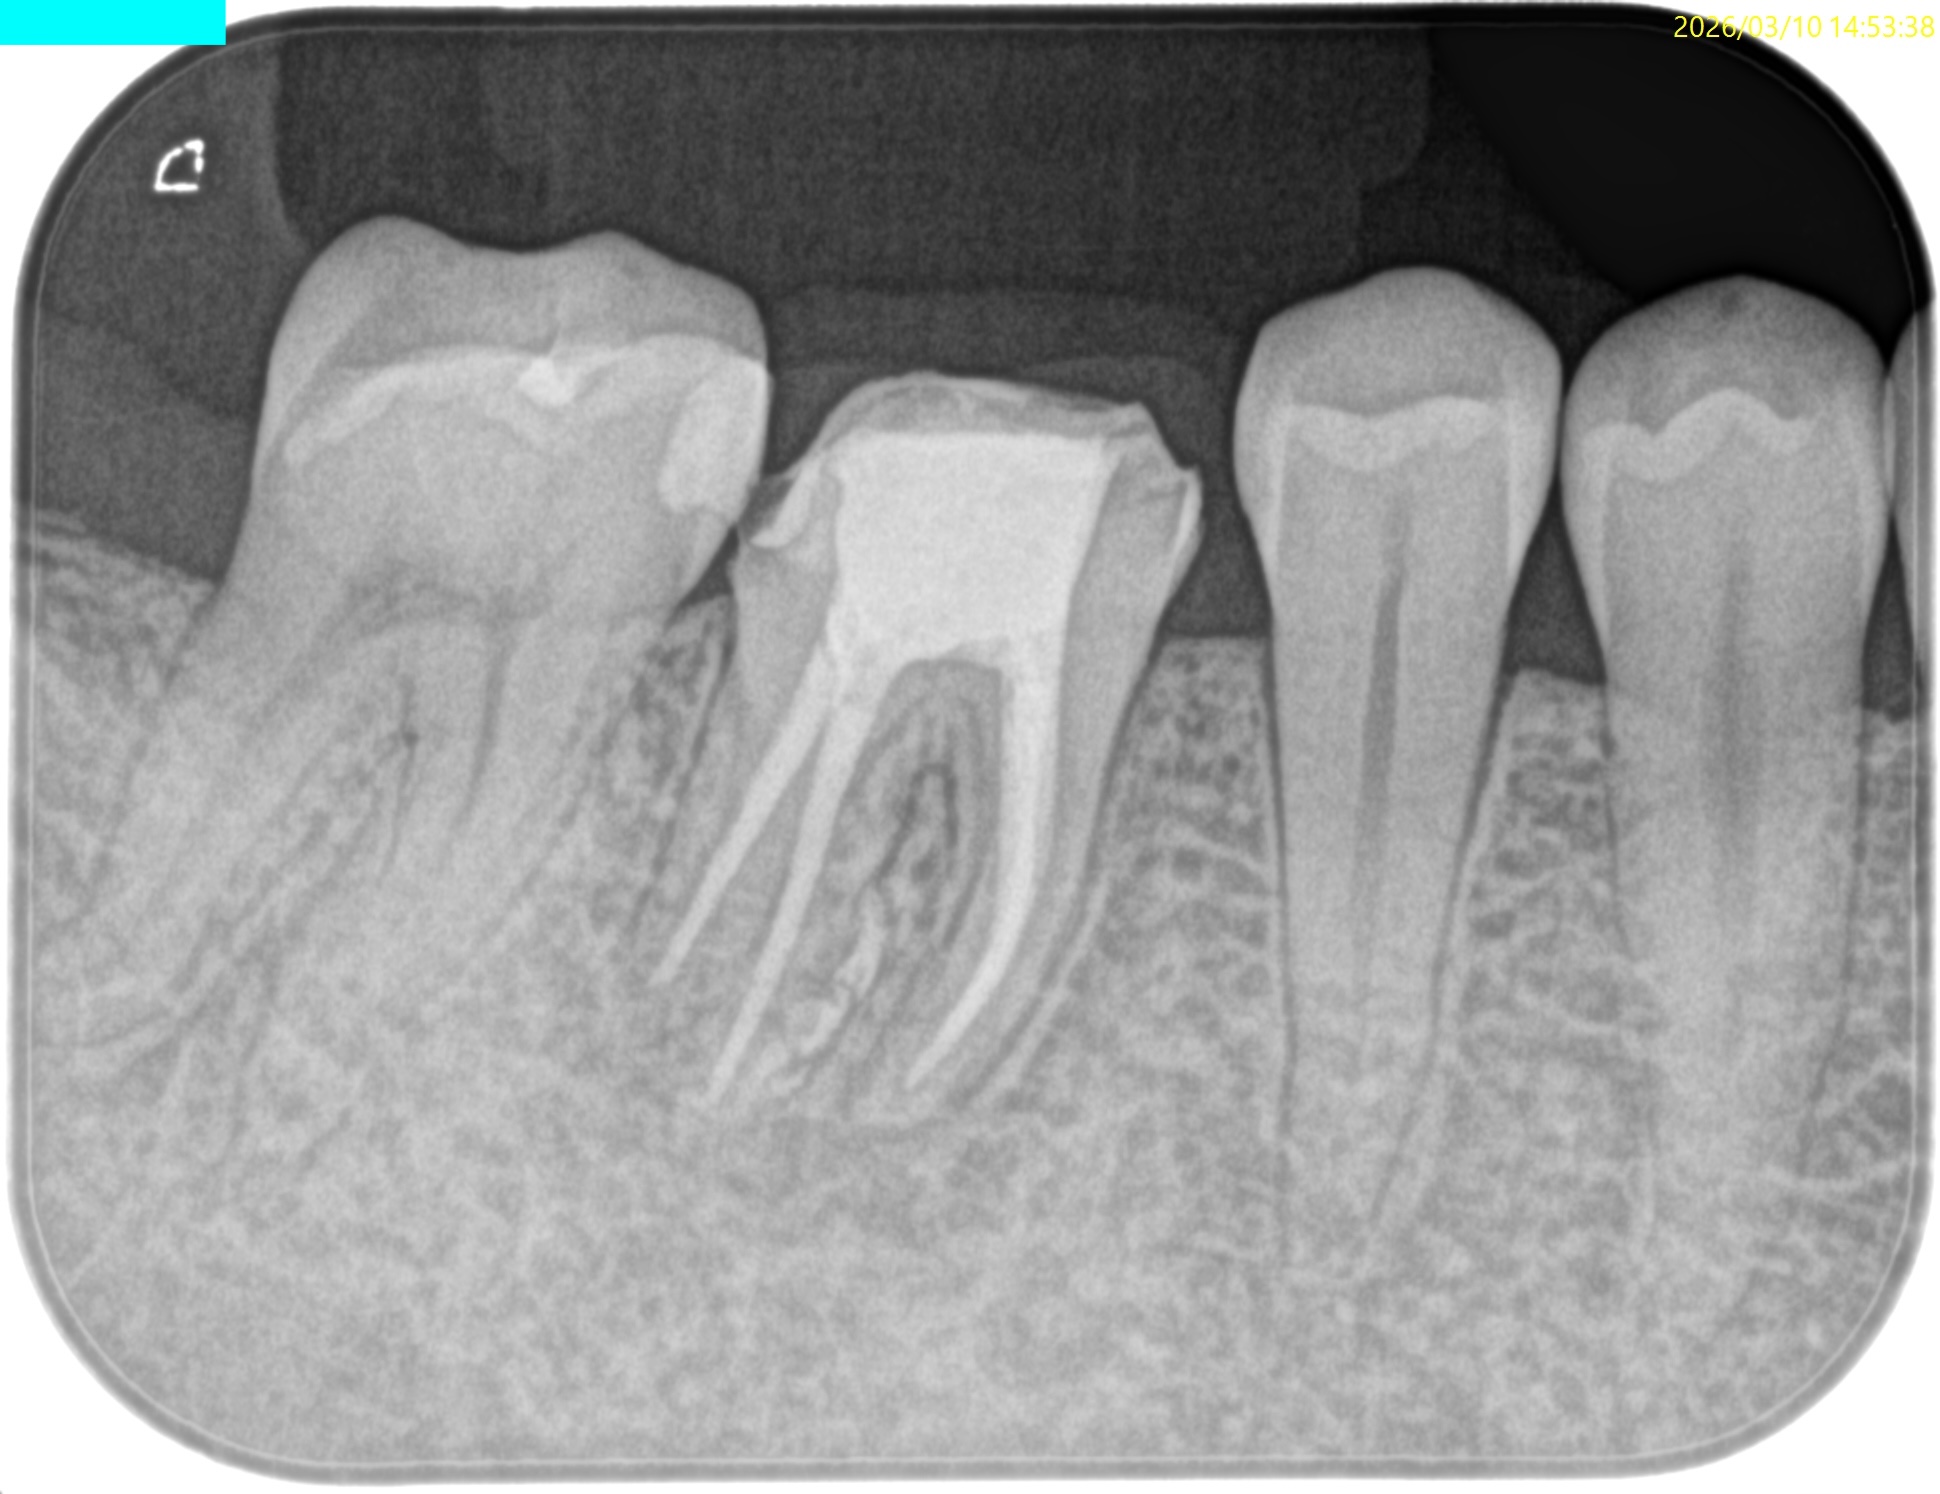

Pre-op Endo test(2025.2.14)

MB

ML

D

Radix

そこそこ湾曲度合いが強いRadix Entomolarisを有する#30だ。

が、D以外の根管はほぼ適切な根管治療がなされていない。

Radixにおいては未着手だ。